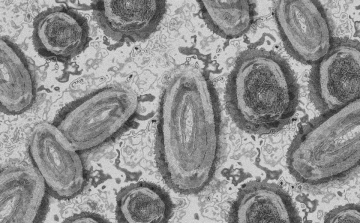

Meghaladta a 13 ezret a majomhimlő-fertőzöttek száma az Egyesült Államokban

Meghaladta a 13 ezret a majomhimlő-fertőzöttek száma az Egyesült Államokban, a legtöbb esetet Kaliforniában és New York államban regisztrálták.

Tovább nőtt a majomhimlő-fertőzöttek száma Magyarországon

Újabb kilenc, 23-50 éves férfinél igazolták a majomhimlő-fertőzést Magyarországon, ezzel 42-re nőtt a fertőzöttek száma - közölte a Nemzeti Népegészségügyi Központ (NNK) csütörtökön az MTI-vel.

Tovább nőtt a majomhimlő magyar fertőzöttjeinek száma

Újabb hat embernél diagnosztizálták a majomhimlő vírusát, így harmincra emelkedett az igazolt fertőzöttek száma Magyarországon - közölte a Nemzeti Népegészségügyi Központ (NNK) pénteken az MTI-vel.

Újabb hét magyarnál igazolták a majomhimlőt

Újabb hét embernél igazolták a majomhimlőfertőzést a Nemzeti Népegészségügyi Központ (NNK) veszélyes kórokozókkal foglalkozó laboratóriumában; ezzel 19-re nőtt az igazolt majomhimlő fertőzöttek száma Magyarországon